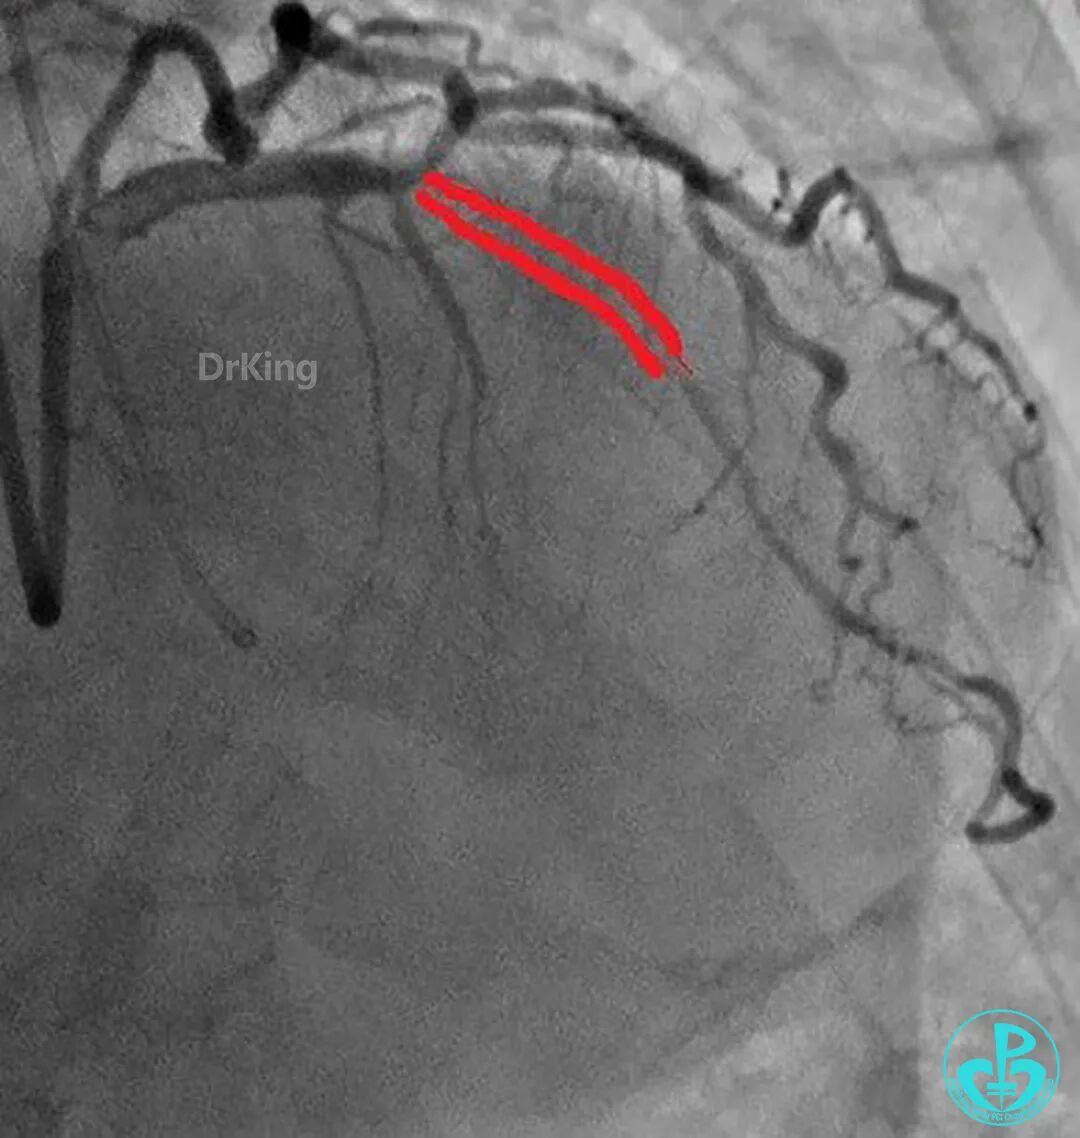

前降支串联植入2.5×30mm、3.0×30mm支架,对角支导丝保护。

出院后1年复查造影,前降支支架通畅,血流3级。患者无明显胸闷、胸痛、喘憋等症状,日常活动不受限制。